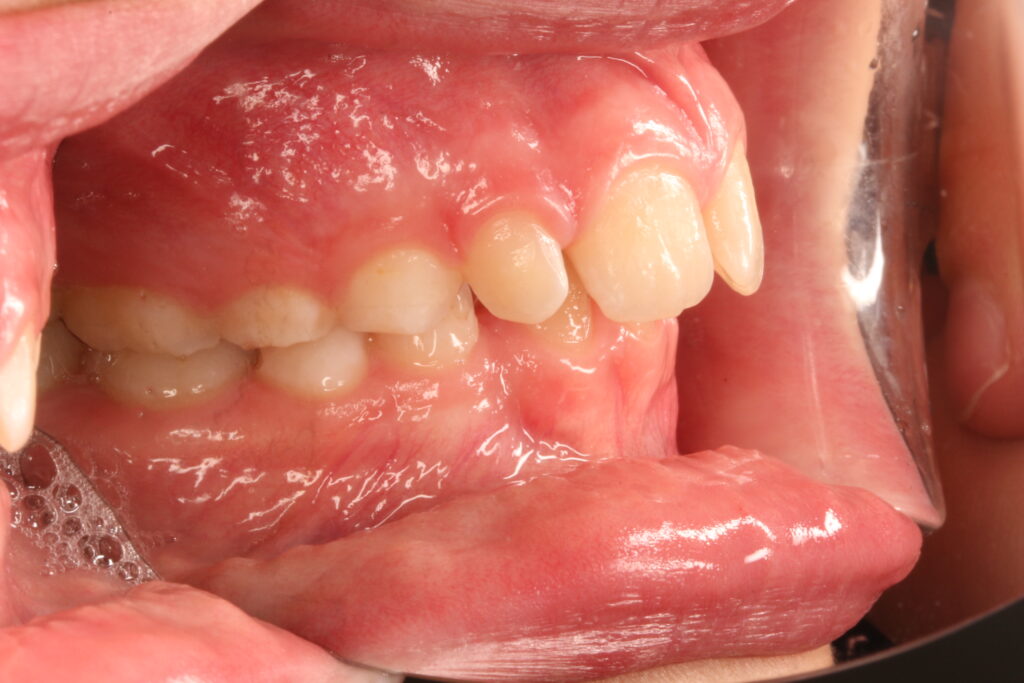

✔ Class II, Class III, aszimmetria és keresztharapás elméleti megközelítése

Az ALF készülék nem az agresszív erőhatásokra, hanem a funkcionális erők finom, biológiailag kíméletes irányítására épít. A klinikai tapasztalatok szerint ez tökéletes elég és mind a fogív fejlesztésében, keresztharapások megszűntetésében, helyteremtésben mind a nyelvtér növelésében jól működik.

A leggyakoribb a vegyes fogazat időszakában (6–11 év), de alkalmazható teljes tejfogazatban is nagyon korai kezelések esetében, akár 3-4 éves kortól is.